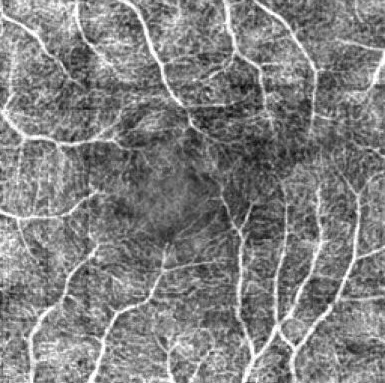

Optical coherence tomography angiography (OCTA) shows its great importance in imaging microvascular networks by providing accurate 3D imaging of blood vessels, but it relies upon specialized sensors and expensive devices. For this reason, previous works show the potential to translate the readily available 3D Optical Coherence Tomography (OCT) images into 3D OCTA images. However, existing OCTA translation methods directly learn the mapping from the OCT domain to the OCTA domain in continuous and infinite space with guidance from only a single view, i.e., the OCTA project map, resulting in suboptimal results. To this end, we propose the multi-view Tri-alignment framework for OCT to OCTA 3D image translation in discrete and finite space, named MuTri. In the first stage, we pre-train two vector-quantized variational auto-encoder (VQ- VAE) by reconstructing 3D OCT and 3D OCTA data, providing semantic prior for subsequent multi-view guidances. In the second stage, our multi-view tri-alignment facilitates another VQVAE model to learn the mapping from the OCT domain to the OCTA domain in discrete and finite space. Specifically, a contrastive-inspired semantic alignment is proposed to maximize the mutual information with the pre-trained models from OCT and OCTA views, to facilitate codebook learning. Meanwhile, a vessel structure alignment is proposed to minimize the structure discrepancy with the pre-trained models from the OCTA project map view, benefiting from learning the detailed vessel structure information. We also collect the first large-scale dataset, namely, OCTA2024, which contains a pair of OCT and OCTA volumes from 846 subjects.